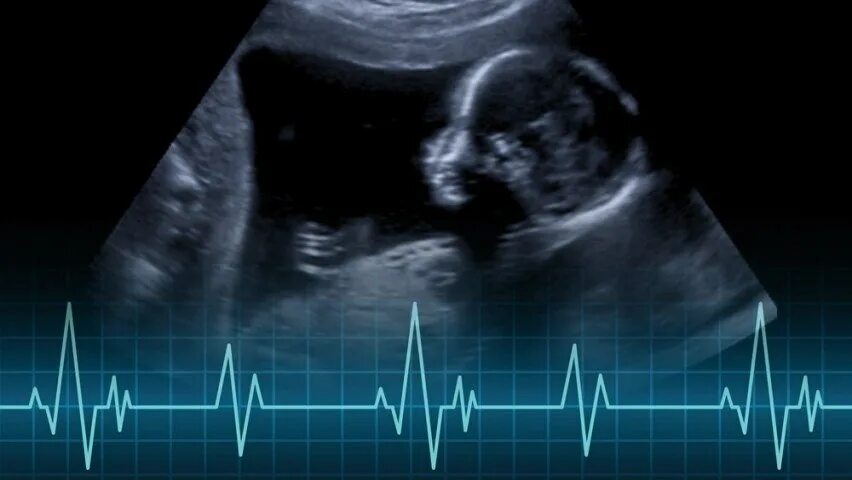

Пульс сердца у детей